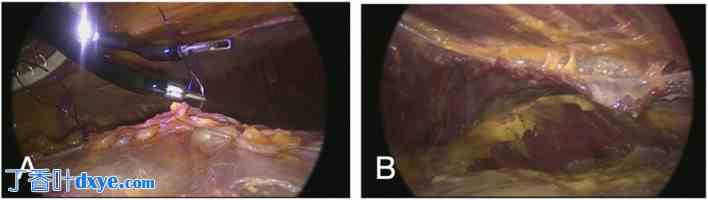

图 6.

腹腔镜图像显示了标记为 A 和 B 的手术视野。图 A 显示了腹腔镜器械操作组织,可见缝合线。图 B 显示了组织内部视图,其中突出显示了各层结构和结缔组织。

在尸体解剖实验室中,使用 SP 小入路端口,通过额外的观察套管,在耻骨上位置进行腹膜外腹直肌后方分离术 (SP2 eTEP),并通过常规腹腔镜观察。缝合后筋膜 (A) 和在膈肌后方、分水岭脂肪上方进行分离所实现的腹直肌后方分离 (B)。